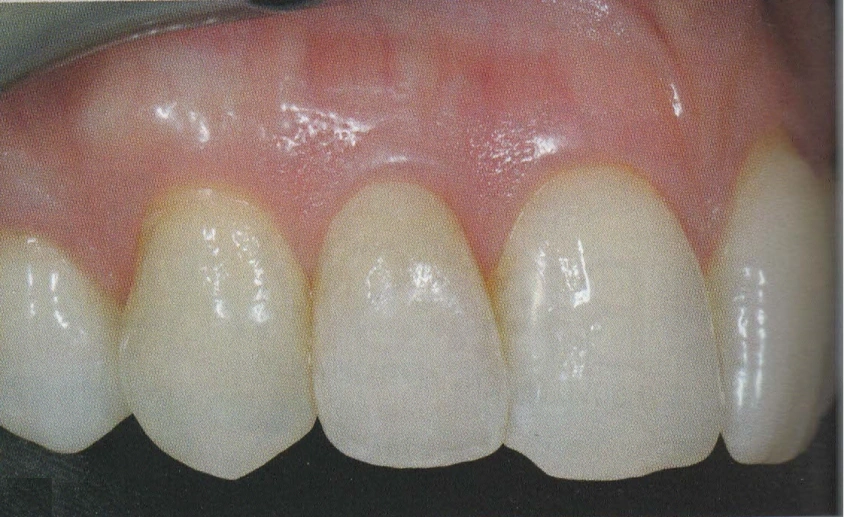

In questo studio vengono eseguite ceramiche di ultima generazione quali la zirconia ceramizzata, le ceramiche estetiche in disilicato senza trascurare le tradizionali metalceramiche. Il disilicato è un materiale altamente estestico che conferisce alla corona protesica un aspetto naturale e con questo materiale si possono creare manufatti con uno spessore molto ridotto.